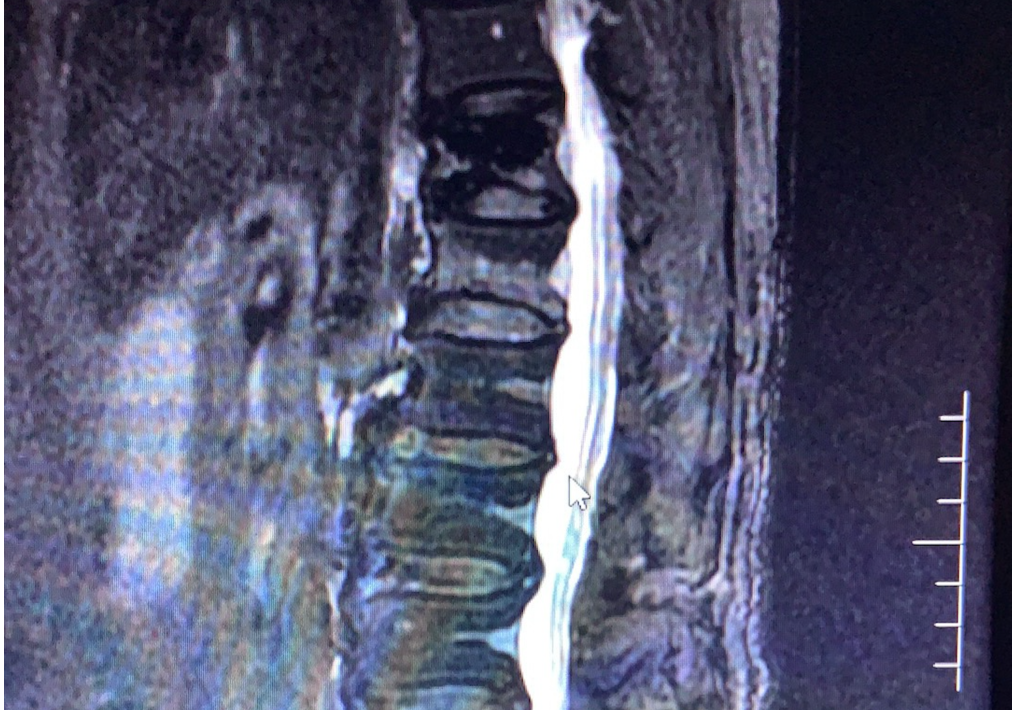

经过反复的询问老人,这个疼痛出现在一周前,老人没有跌倒过,但是在家里搬了比较重的一盆水。当时感觉可能扭了一下腰,之后腰部出现了非常剧烈的疼痛,和之前摔倒后做手术前疼痛是一样的。家人非常紧张,于是赶快到医院就诊。患者在外院的普通的x线片上没有发现很明显的骨折。由于疼痛比较剧烈,我们还是请老人家去做了磁共振,结果发现脊椎的另外一节椎体上出现了比较明显的骨折信号(见下图)。老人这次卧床休息了几天之后,疼痛出现了一些缓解。后面又带了几天孙子,疼痛程度有所加重,范围也有所扩大,最后不得已,再次进行了微创手术,才恢复了健康。